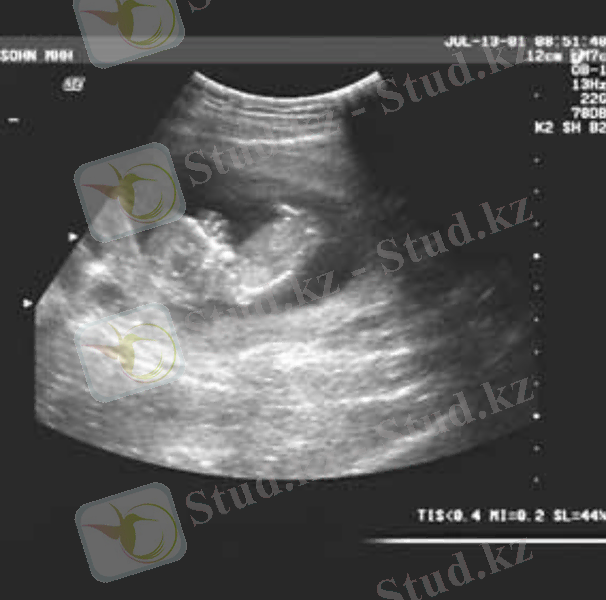

Ультрадыбыстық зерттеу (Инвазивті емес ПД)

Ұрықтағы туа біткен ақаулықтарды (ОЖЖ, аяқ-қолдардың, жүрек-қан тамырлар, зәр шығару, АІЖ, өкпе) анықтауға мүмкіндік береді.

Өткізу уақыты - 10-20-30 апталарда.